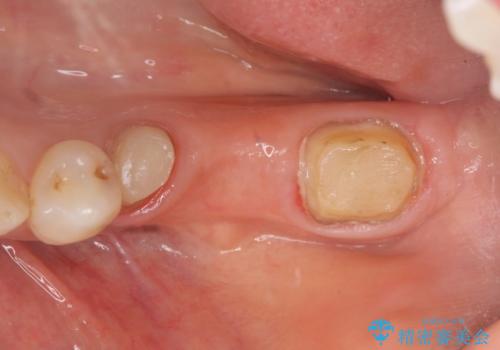

左下7の遠心部は部分的な骨欠損によるポケットが10mmあったため、再生療法による骨の再生を行いました。

骨の定着を待ちポケットが3mm(正常範囲内)であることを確認後、オールセラミッククラウンによる欠損補綴を行いました。

再生療法とは歯槽骨の欠損部位を人工骨で補うことにより骨を再生させる手術です。

この手術を行うことで、歯周基本治療では治癒しない歯周病を改善したり、本来ならば抜歯しなければならない歯を保存することができます。